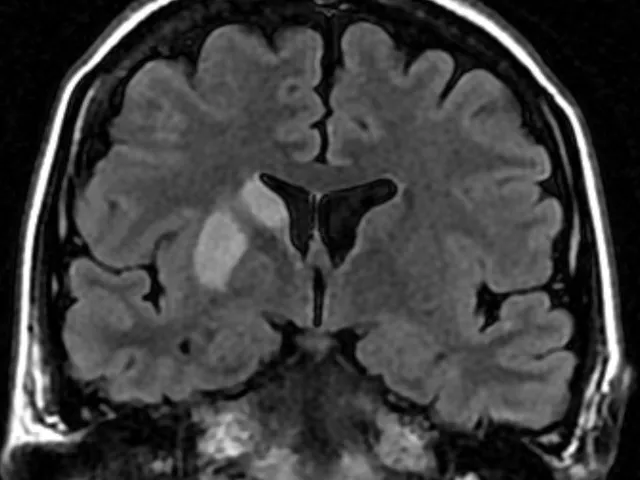

The goal of the fellowship is to increase the participants' confidence and competence in interpreting imaging studies of the brain and its coverings, head & neck, as well as the spine. This will be achieved by analyzing and discussing various possible sources of both error and additional relevant information.